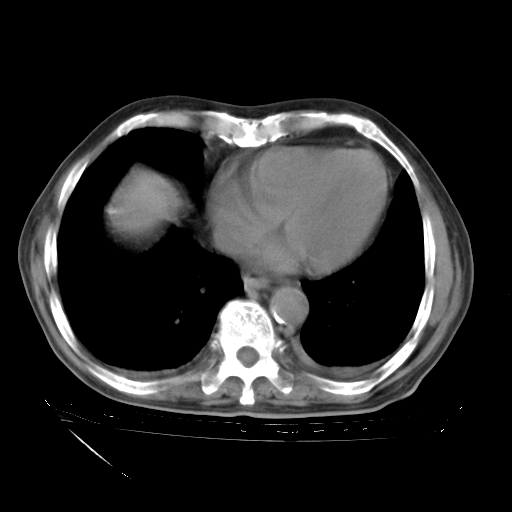

甲强龙80mg/日+抗结核治疗(异烟肼+利福霉素+乙胺丁醇)10天。复查肺部CT。

治疗10天肺部CT